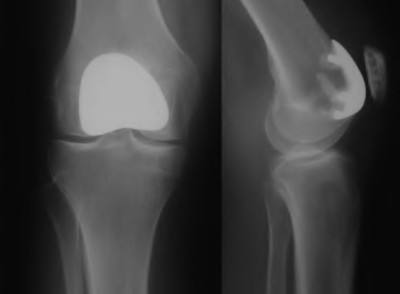

A patient presents with persistent anterior knee pain and a 'clunking' sensation 1 year following a primary total knee arthroplasty. On physical exam, the patella tracks laterally and there is tenderness over the lateral retinaculum. Radiographs and CT scan are obtained. Which of the following component malpositions is most likely responsible for lateral patellar maltracking?

Explanation